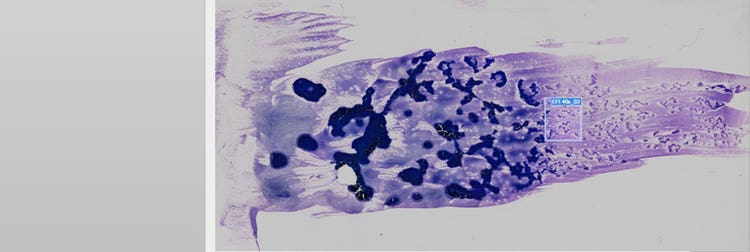

Imagerie sur lame entière d’un échantillon de sang périphérique

Figure 1. Échantillon de sang périphérique humain d’un patient atteint de leucémie aiguë promyélocytaire numérisé avec le scanner de lames pour la recherche VS200. Images reproduites avec l’aimable autorisation de Jana Kirsten de l’Institut de chimie clinique et de médecine de laboratoire du Centre médical universitaire de Ratisbonne.

Dans cette application, le sang périphérique montre les promyélocytes néoplasiques avec des noyaux bilobés ou des granules abondants (figure 2, flèche orange). Ces promyélocytes néoplasiques sont également présents dans la moelle osseuse, ainsi que des myéloblastes dans lesquelles se trouvent des faisceaux entiers de bâtonnets d’Auer (flèche verte en A, B et C). Ces éléments sont importants à rechercher en cas de suspicion de LAP.

Imagerie de myéloblastes avec des bâtonnets d’Auer par numérisation d’une lame entière

Figure 2 : (A) Myéloblaste avec bâtonnets d’Auer acquis à un grossissement de 40X mais zoomé numériquement à 60x. (B) Même blaste acquis à un grossissement de 60X et affiché en résolution native. (C) Même image que A, mais avec la résolution native de 40X. (D) Blaste avec granules à un grossissement de 60X.

La comparaison de l’image A (40X) avec B (60X) dans la figure 2 montre l’avantage de l’objectif à huile UPLXAPO 40X avec une ON de 1,4, car les bâtonnets et les granules sont encore clairement visibles à ce grossissement inférieur. De plus, le temps de numérisation avec l’objectif 40X était 50 % plus court qu’avec l’objectif 60X (temps de numérisation pour une surface de 1 × 1 cm : 40X = 4 minutes 40 sec, 60X = 10 minutes 30 sec).